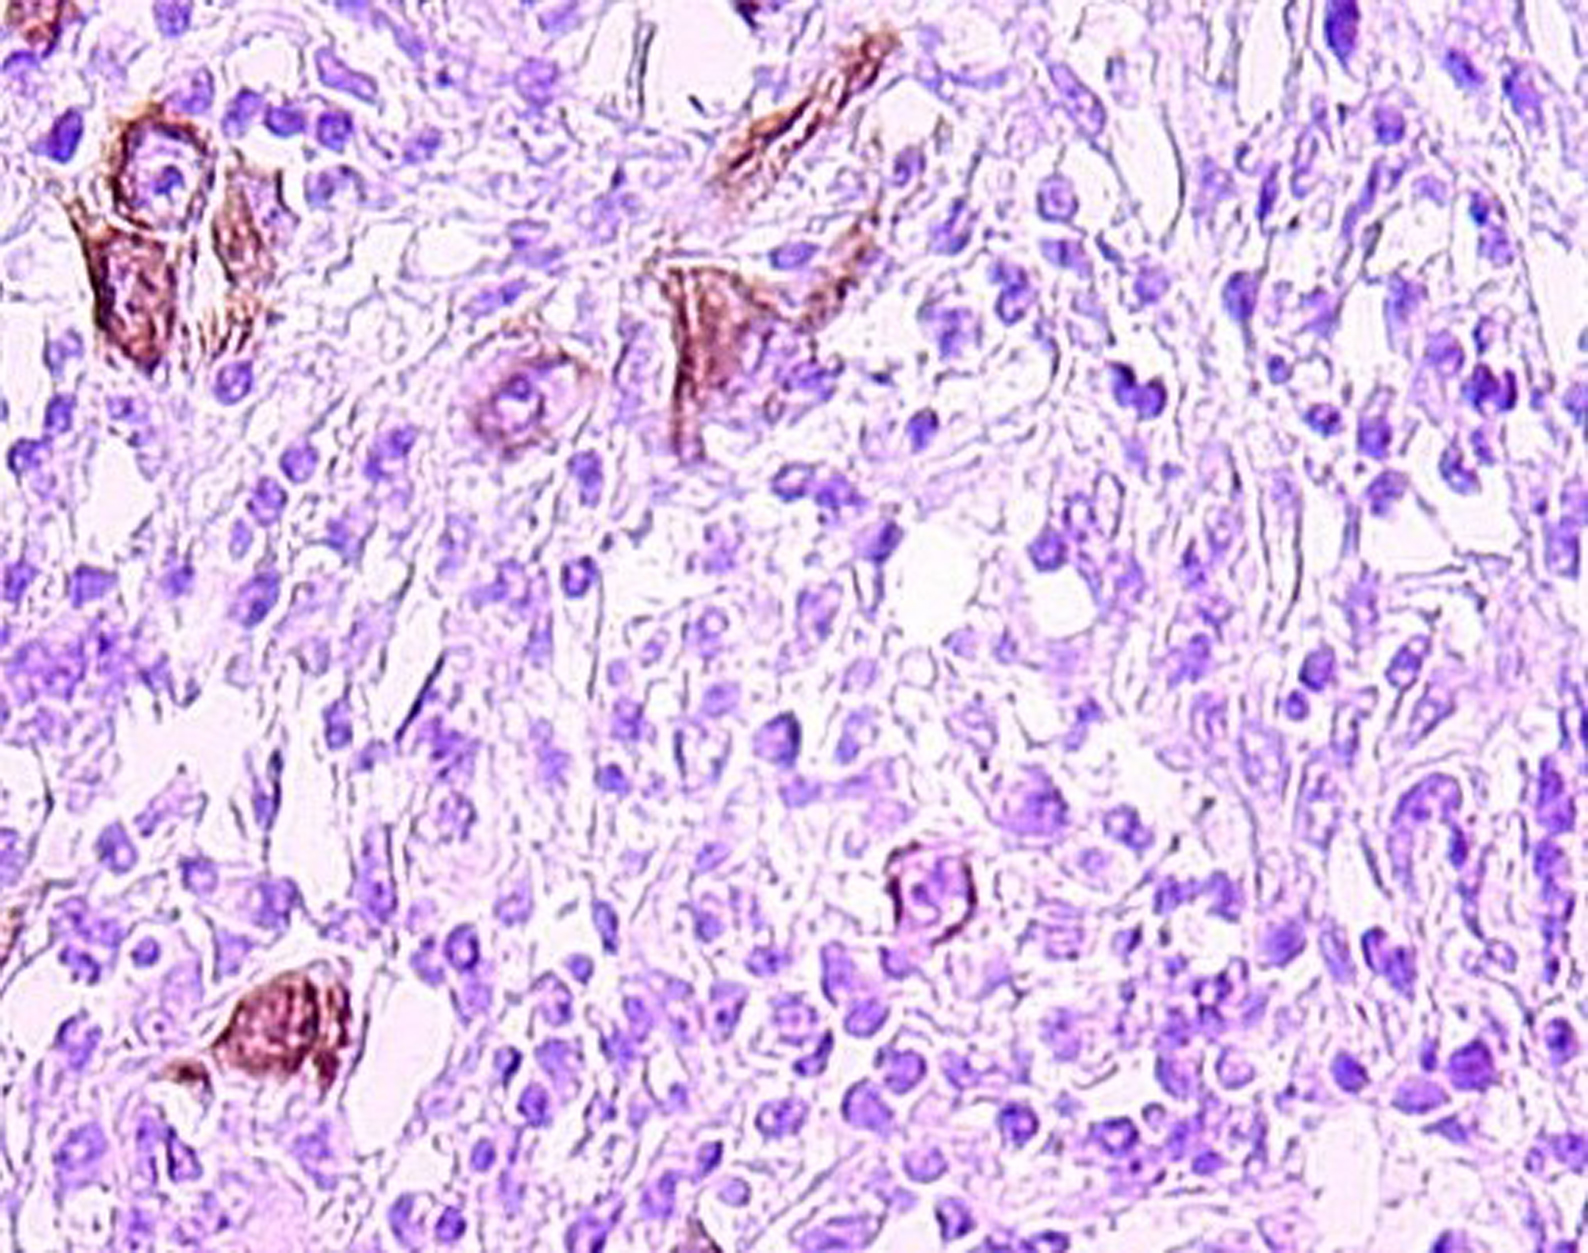

A 58-year-old Tunisian man with no medical history presented with a two months' history of left nasal obstruction and one episode of epistaxis. Nasal endoscopy revealed a smooth reddish polypoid mass of the nasal septum. The mass bled easily whenever palpated by the instrument. There was no evidence of lymph node metastasis. Magnetic resonance imaging (MRI) showed a 30 x 50 mm left nasal cavity tumor with erosion of the orbit (Fig. 1). The tumor was found to originate from the nasal septum. Histological examination of the biopsy demonstrated a tumor proliferation that was made of irregular sheets, islands and single neoplastic cells richly infiltrated by lymphocytes and plasma cells. Epithelial component consisted of large cells with indistinct cell borders resulting in syncitial appearance (Fig. 2), vesicular nuclei and moderate mitotic activity (Fig. 3). Necrosis and keratinization were absent. Immunohistochemically, most of tumor cells were positive for cytokeratin and epithelial membrane antigen (EMA) (Fig. 4). The surrounding cellular infiltrate was a mixture of CD20 and CD3 positive B and T lymphocytes. Immunohistochemical expression of EBV latent membrane protein 1 (LMP1) and in situ hybridization to EBV encoded RNA were positive. The diagnosis of primary LEC NC EBV positive was performed after excluding metastatic nasopharyngeal undifferentiated carcinoma of the nasal cavity by random biopsies from the nasopharyngeal mucosa. The tumor was classified T4N0M0. Systemic chemotherapy was started and consisted in intravenous Adriamycin and Cisplatin. Radiotherapy was done based on 72 Gy in the tumor and 52.2 Gy in the bilateral cervical lymph node region: 1.8 Gy/day, 5 days per week. The patient remains alive and disease free 12 months after treatment.

![]() Click for large image | Figure 4. Tumor cells immunoreactivity with EMA antibody (IHC x 400). |